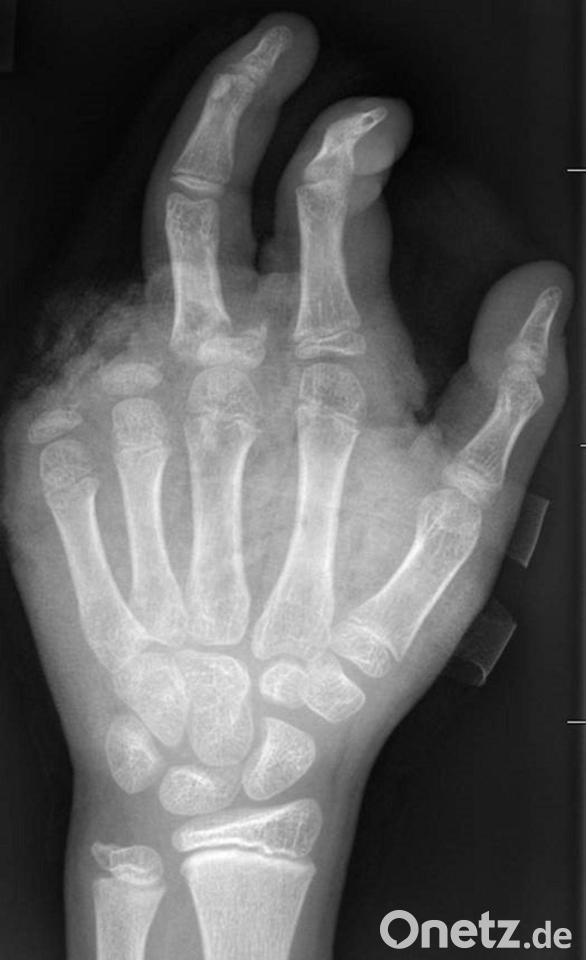

In der Handchirurgie müssten an Silvester im Unfallkrankenhaus rund 20 bis 40 Menschen mit Böllerverletzungen operiert werden, sagt die Ärztin. Dieses Jahr werde sie mir vier weiteren Handchirurgen im Einsatz sein. Die häufigsten Verletzungen entstünden durch explodierende Böller in der Hand.

„Der überwiegende Teil der Verletzungen trägt tatsächlich lebenslange Folgen mit sich, weil die Sprengkraft dazu führt, dass eben nicht nur einzelne Strukturen verletzt sind, sondern immer mehrere. Und das heilt praktisch nie ganz folgenlos ab.“ Zum Teil könnten Hände nicht mehr gerettet und müssten amputiert werden.